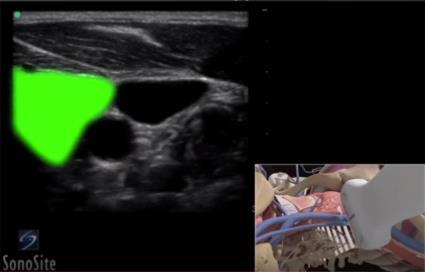

Vascular Thyroid Gland Highlighted Image

Highlighted Area: Thyroid Gland